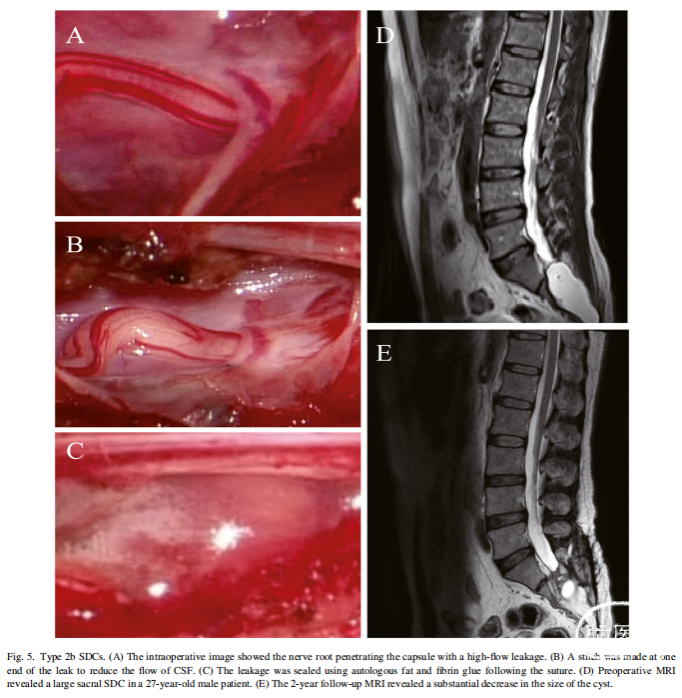

手术策略

对于不同亚型的囊肿,我们制定了相对应的手术策略。1a型SDC裂隙型漏口采用直接细线缝合,而1b型孔径型漏口采用补片或自体组织修补缝合。2a型的低流量渗漏直接用自体脂肪和纤维蛋白胶进行封堵。对于高流量的2b型,先在漏口末端缝合一针或两针,使脑脊液流量降低到类似2a型的低水平,然后用脂肪和纤维蛋白胶封堵。

2b型,为高流量泄漏

37例2型SDCs确诊为高流量渗漏,进行了端口缝合,随后进行了封堵(图5A-C)。36例患者症状明显改善,1例患者无明显变化。随访MR显示7例(18.92%)囊肿消失,29例(78.38%)囊肿明显缩小(图5D, E)。

对于低流量的2a型,可以用自体脂肪和纤维蛋白胶直接封堵渗漏。但2b型CSF流速较快,单纯用脂肪和纤维蛋白封堵不够牢固,可能导致术后脑脊液漏出和囊肿复发。在漏口末端进行缝合,可以有效地将高流量降低到低水平,从而提高封堵的成功率。在大多数情况下,在漏口的一端缝合一针就足够了,如果流量仍然很高,可以在另一端加缝一针。文献报道经介入治疗或开放手术,83.5%的Tarlov囊肿患者总体症状改善。本组2型SDCs经2年多的随访,症状改善率达到97.59%。我们这组病例队列中囊肿复发率和总并发症发生率与介入性或开放性手术相比都较低。尽管评价标准可能存在一些差异,我们的数据表明,显微封堵技术治疗2型SDCs取得了更好的结果。